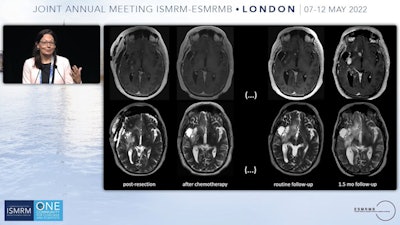

Smits provided an example of the type of patient who could benefit. She showed brain MRI scans of a patient whose tumor was resected, with no significant findings after chemotherapy. However, on a routine follow-up T2-weighted abnormalities appeared to increase, and a month later, another exam revealed the tumor had fully returned. Something happened to the tumor that made it nonresponsive to treatment, Smits said.

"We would like to know what changed because then of course we can adapt the treatments, and we won't be taking a tissue sample every time we follow these patients up," Smits said.